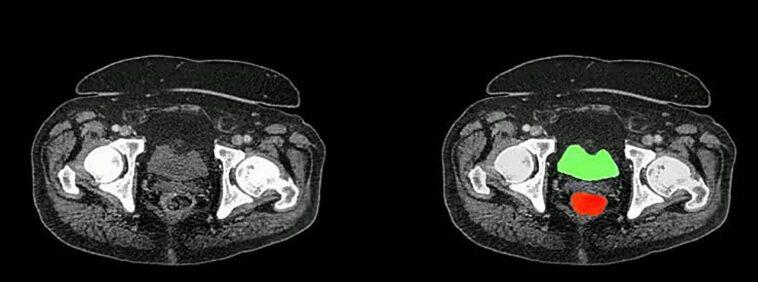

The field of medical imaging is experiencing a revolution, thanks to advancements in artificial intelligence (AI). Johns Hopkins researchers have introduced AbdomenAtlas, an AI-powered dataset that promises to dramatically enhance medical image analysis. With 45,000 3D CT scans annotated with 142 anatomical structures, this dataset represents a breakthrough in early cancer detection and medical AI training.

- 10-fold improvement in tumor identification efficiency.